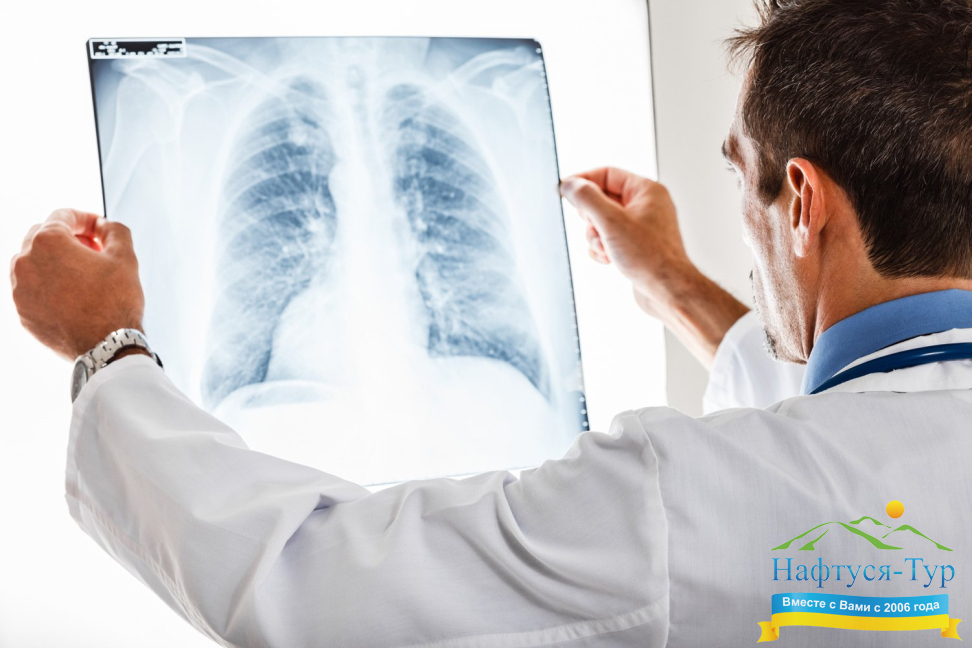

Строго говоря, Рентген – это фамилия ученого, который открыл электромагнитное излучение определенного диапазона, способного проникать через многие препятствия (например, проходить через тело человека), а затем засвечивать, оставлять изображение на фотопластинке. Благодаря этому такие диагностические методы, как рентгенография, рентгенологическое исследование, сегодня значатся в перечнях возможностей практически любого санатория и медицинского учреждения, а посетители данных заведений часто сокращают их официальное название до «Рентген». Рентгенологическое исследование является неинвазивным, оно подразумевает лишь строго дозированное вредное лучевое воздействие на человеческий организм. Данный вид диагностических исследований позволяет получить изображения внутренних органов, определить наличие в них патологий. Добавим, что рентгенография постоянно развивается, использование при диагностике компьютера позволяет получать значительно более широкий перечень информации, необходимой для определения и лечения недуга.